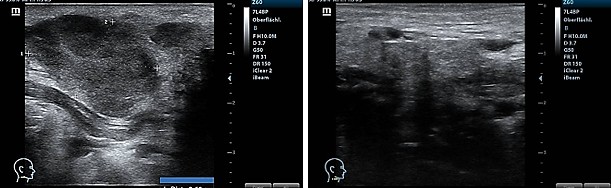

After five years of being free of symptoms, a rapidly growing, parotid-adjacent tumor on the right side occurred leading to facial palsy. An attempt to surgically remove the tumor was aborted due to risk to the facial nerve. An F-18-FDG PET whole-body CT scan revealed several disseminated hepatic metastases, osseous metastases in the pelvis and in the 5th dorsolateral rib. Histology of a biopsy from a hepatic metastasis as well as from a biopsy of the osteolytic region at the 5th rib, confirmed a recurrence of malignant melanoma. At this moment, the patient was in significantly reduced general condition with bad prognosis. The patient has been receiving oncological combination therapy with two immune checkpoint inhibitors, Ipilumab and Nivolumab. In parallel, an ultrasound-guided, once-weekly piezoelectric TMI treatment in the right parotid region was initiated. For this purpose, the PiezoWave2 device was used with a gel pad (shallow penetration depth Gelpad Nos. 5 and 10). The frequency used was between 2 and 4 Hz per treatment, with 3 Hz being the most common frequency. Depending on pain sensitivity and tolerance, 1000-1500 impulses were applied per session with an energy flux density of 0.12 mJ/mm². Following four immune checkpoint combination therapy sessions and eleven treatments with piezoelectric TMI treatment, a distinct regression after two months and a complete remission of the parotid-adjacent tumor as well as complete concomitant remission of the facial palsy occurred within four months (Fig. 3). Alongside the TMI treatment of the parotid region, TMI treatment of the pelvis metastasis using the PiezoWave2 device was performed simultaneously, precisely localizing the metastatic area measured in the PET-CT scan and based on patient-specific FEM simulation analyses. The deepest penetration depth was achieved with Gelpad 60, at a frequency of 2 Hz. Each treatment delivered 3000 impulses with an energy flux density of 0.35 mJ/mm². In a CT scan six months later, a significant reduction in bone metastases was observed as well as a complete remission of the hepatic metastases not directly treated with shock waves; however, a new pelvic metastasis had occurred. The metastasis at the 5th rib had disappeared (Fig. 4). Though the patient was affected by both the oncological disease and the side effects of the drug therapy, to consolidate and continue the evident therapeutic efficacy, regular TMI treatment of the new metastasis in the pelvic region was resumed with the OrthoGold100® device. The patient was treated 14 times over a six-month period. Each treatment involved a combination of the focused technique with the dark blue applicator and the non-focused technique with the yellow applicator. The deepest penetration depth was selected, along with energy flux density of 0.18 mJ/mm² or 0.27 mJ/mm², applying 2000 impulses per applicator, thus a total of 4000 impulses per session. After TMI treatment, native CT scans showed a distinct regression of the new pelvic metastasis and unchanged sclerosis of the known bone metastases.

Fig. 3

Fig. 3: Sonography of the parotid-adjacent tumor before TMI treatment (left) and regression two months later after TMI treatment (right).